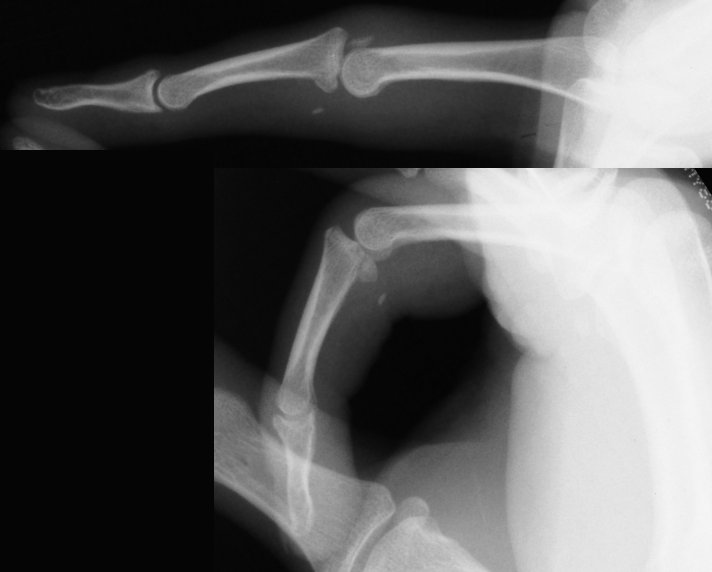

Xrays show a comminuted dorsal fracture dislocation of the proximal interphalangeal joint with dorsal subluxation.

The joint moves, but through an unnatural hinging on the edge of the fracture.